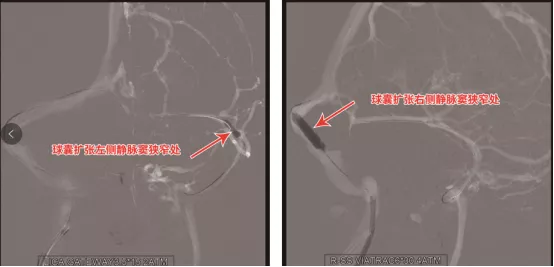

隨後靜脈竇狹窄擴張成形及支架置入術。這是一項難度較高的血管介入手術,因為顱內靜脈竇重度狹窄,甚至有的血管還呈九曲連環狀,要將支架準確無誤地放在靜脈竇狹窄處非常困難,稍有不慎便會造成患者血管損傷,乃至生命危險。劉加春主任決定在左側左側橫竇—乙狀竇交界段行球囊擴張成形術,在右側的優勢引流血管——右側乙狀竇行支架置入術,既保證患者效果,也為患者減輕經濟負擔。

術中,劉加春主任準確無誤地定位病灶後,嫻熟地操縱著微導絲,先沿著微導絲將球囊擴開左側橫竇及乙狀竇狹窄段,造影顯示狹窄部分改善。再沿著微導絲將球囊擴張右側乙狀竇處,再送入支架,最後精準地釋放在狹窄段,撤出釋放裝置後再次造影可見狹窄解除, 支架貼壁良好,狹窄的靜脈竇便得以充分開啟。再次用壓力導絲測壓,各靜脈竇無明顯壓力差,證實手術有效地解除了靜脈迴流障礙。術後,小吳也感覺頭痛、頸痛較術前明顯緩解,視力也較前有所恢復。術後第5天的腰穿測壓也證實,小吳的顱內壓已經降下100mm多水柱。